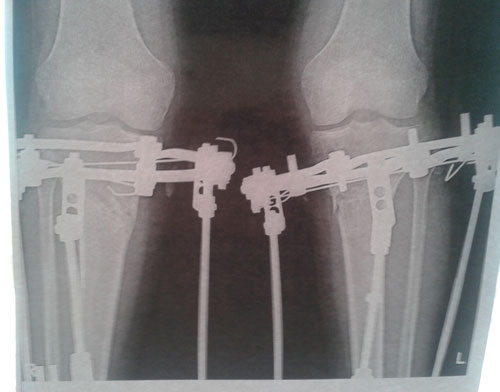

Дата операции 29.08.2013г.

Дата снятия аппаратов 04.12.2013г.

Срок лечения 95 дней.